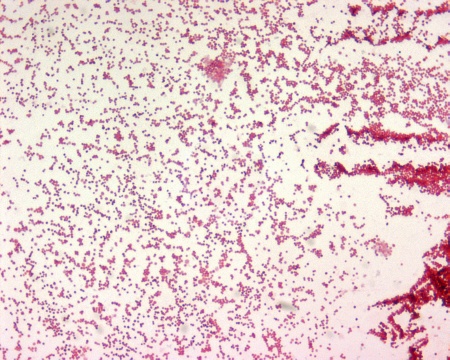

BeSt programmi raames loodud õpiobjekt aitab iseseisvalt õppida viirusinfektsioonide tekitajate nimesid, morfoloogiat, klassifikatsiooni ja omadusi ning annab ülevaate ka viirusnakkuste patogeneesimehhanismidest, profülaktika- ja raviprintsiipidest. Materjal on mõeldud selleks, et toetada üliõpilaste iseseisvat õppimist ja anda neile võimalus oma teadmisi testida.

BeSt programm, sisupakett, meditsiiniline mikrobioloogia, puuk, puukborrelioos, Lyme’i tõbi, puukentsefaliit, anaplasmoos, erlihhioos, tulareemia, babesioos